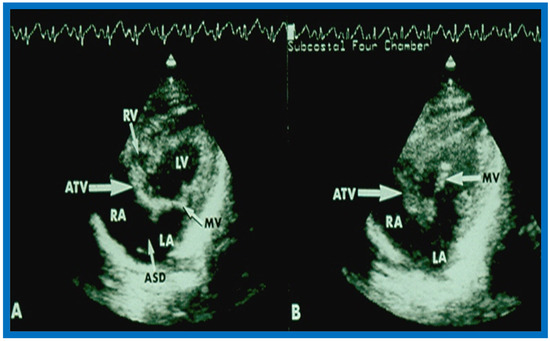

6. Echocardiographic Features of Tricuspid Atresia

The M-mode and two-dimensional echocardiographic features of tricuspid atresia were discussed in the author’s first book on tricuspid atresia, written in collaboration with his colleague, Dr Wesley Covitz at the Medical College of Georgia [7]. The two-dimensional (2D) echocardiographic pictures in 1982 were crude (Figure 14) [7]; however, they represented the state of the art echocardiography machines of that time.

Figure 14.

Selected video frames from apical four-chamber view of a two-dimensional (2-D) echocardiographic study demonstrating dense band of echoes between the right atrium (RA) and hypoplastic right ventricle (RV). Line drawings are shown beneath the 2D frames. Note that the mitral valve is closed in the left image while it is open in the right image. The atretic tricuspid valve echoes remain unchanged. LA, left atrium; LV, left ventricle. Reproduced from Covitz W., Rao P.S. [7].

Figure 15.

Selected video frames from subcostal four-chamber view of a two-dimensional (2-D) echocardiographic study demonstrating atretic tricuspid valve (ATV) (thick arrow), represented by a dense band of echoes between the right atrium (RA) and hypoplastic right ventricle (RV). In (A), the mitral valve (MV) is closed, while in (B), it is open. Note the improvement from the pictures shown in Figure 14. LA, left atrium; LV, left ventricle. Reproduced from Rao P.S. [35].

Figure 16.

Apical four-chamber view pictures of another infant with tricuspid atresia (large arrows in A,B) with ostium primum atrial septal defect (slanted arrow in B). Note small right ventricle (RV) and a ventricular septal defect (small arrows in A and B). LA, left atrium; LV, left ventricle; RA, right atrium. Reproduced from Covitz W., Rao P.S. [36].